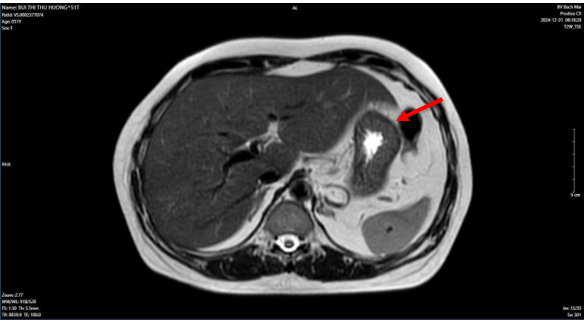

- Chụp cắt lớp vi tính lồng ngực:

Chẩn đoán xác định:

Ung thư biểu mô tuyến thùy trên phổi phải, di căn hạch cT1N3M0 giai đoạn IIIB/ Tăng huyết áp